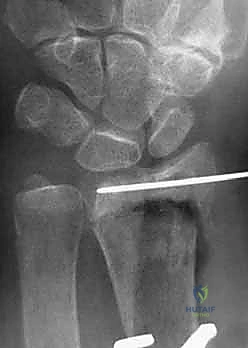

4. وضع الصفيحة والتثبيت المؤقت

يتم اختيار صفيحة تيتانيوم مصممة تشريحياً لتلائم انحناء الكعبرة. توضع الصفيحة على العظم وتُثبت مؤقتاً بأسلاك معدنية دقيقة (K-wires).

5. حفر العظم ووضع المسامير

يتم حفر ثقوب في العظم عبر فتحات الصفيحة، ثم تُقاس المسافات بدقة لإدخال مسامير القفل (Locking Screws) في الجزء البعيد (قرب المفصل) ومسامير قشرية في الجزء القريب (في ساق العظم).

6. الفحص النهائي والإغلاق

يتم إجراء فحص أخير بالأشعة للتأكد من المحاذاة المثالية للكسر وأطوال المسامير (لضمان عدم بروزها واحتكاكها بالأوتار الخلفية). بعد ذلك، يتم خياطة الأنسجة والجلد بخيوط تجميلية ووضع ضمادة معقمة.